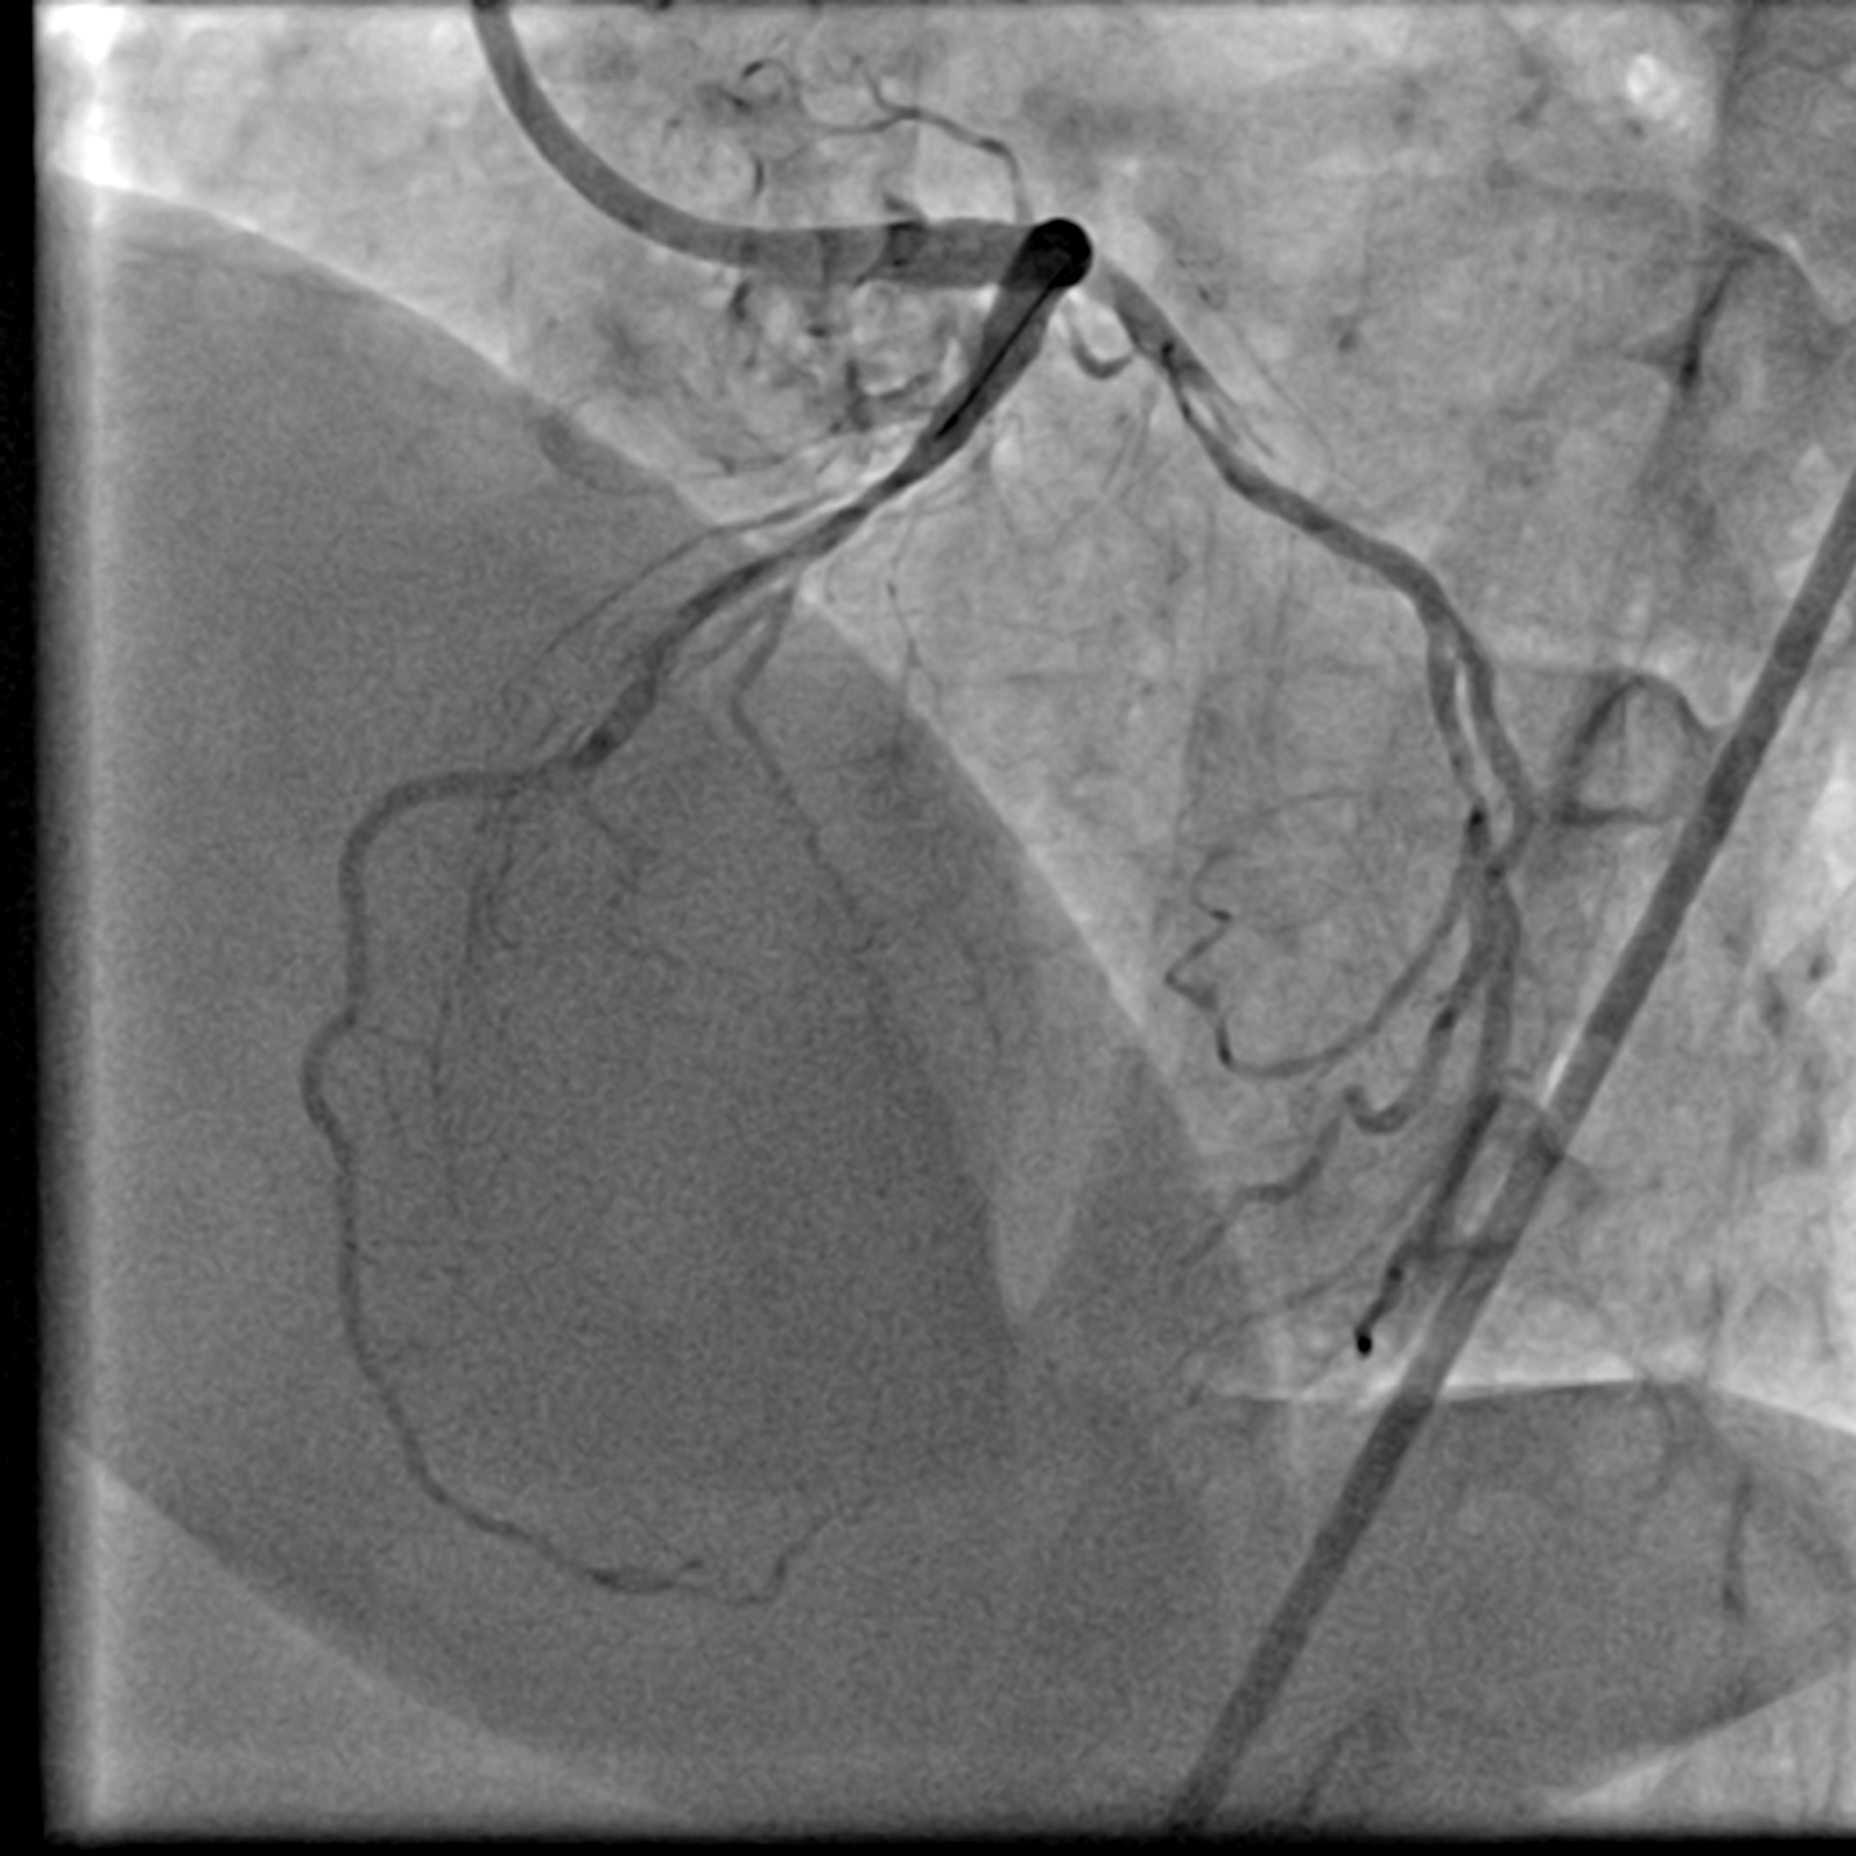

The Right Coronary Artery only had mild disease. There was a Left Main Stem (LMS) bifurcation lesion involving the ostium of the Left Anterior Descending (LAD) artery and the Left Circumflex (LCx) artery (Medina 1,1,1). A conspicuous calcification was visible on fluoroscopy. Intravascular Ultrasound (IVUS) was utilized to further assess the lesion. Its findings correlated with those from fluoroscopy. Specifically, a calcium nodule was identified at the ostium of the LCx in the anti-carina area.

LCA AP Cran 1.mp4

LCA LAO Caud 1.mp4

LCA AP caudal.mp4